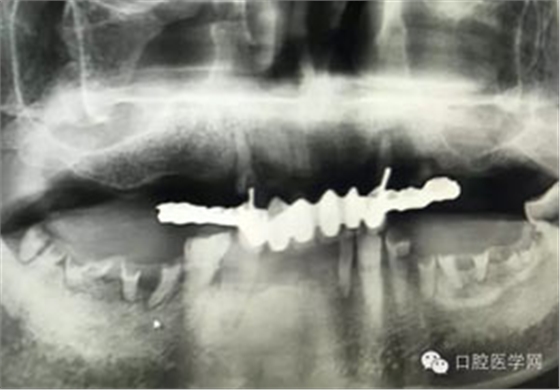

病例1:患者迫切希望保留自己的這一顆牙齒,根尖周陰影比較大,二度松動(dòng).而且旁邊有種植修復(fù)體,和患者溝通好后,治療好后觀察一個(gè)月后冠修復(fù),因?yàn)橛蟹N植的后期修復(fù),所以有了機(jī)會(huì)觀察,術(shù)后三個(gè)月和術(shù)后四個(gè)月,根尖恢復(fù)的還算不錯(cuò),希望能夠繼續(xù)觀察下去.這樣子的病例,做的時(shí)候我們一定要非常的小心,和患者要有充分的溝通以及不同科室的溝通然后決定怎么樣做比較好,假如就是出現(xiàn)了問題,到時(shí)候我們也比較好處理些,免得我們自己到時(shí)候不好收?qǐng)觥?/span> 病例2:364647中齲的樹脂充填,現(xiàn)在樹脂的充填材料非常之多,有些時(shí)候,我們感覺有了好的材料我們就可以做出好的修復(fù),可是這是在我們有扎實(shí)的基本功的基礎(chǔ)上的,我們可以沒有那么好的樹脂,那么多的顏色選擇,修復(fù)的那么的逼真,但是我們至少要恢復(fù)患者牙齒的功能,將腐質(zhì)去除干凈,薄壁弱尖消除掉,選擇好適應(yīng)癥,給患者以盡可能好的修復(fù)。 來源于KQ88